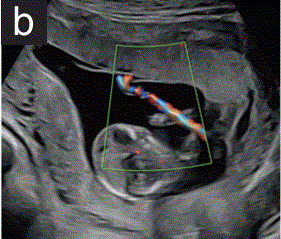

静脉导管通常在偏右侧切面上进行评估。彩色多普勒用于识别通过脐静脉和静脉导管返回到右心房的血流。一个1mm的脉冲波多普勒门可以用来显示波形,它具有一个典型的外观(图1f)。PIV是通过自动跟踪来测量的。

胎儿mt是什么检查什么疼吗【文献学习/规范指南】ISUOG实践指南(2023更新): 11-14周胎儿超声检查(全文)_https://www.jmylbn.com_新闻资讯_第31张

图1 11+0至14+0周胎儿超声检查可获得的测量值。

(f)胎儿胸部和腹部的旁矢状面图,彩色和脉冲多普勒,显示脐静脉和静脉导管(DV)的血流。在正常情况下,DV速度波形是三相的,在收缩期(S)、舒张期和舒张期末(a波)有顺行流动。